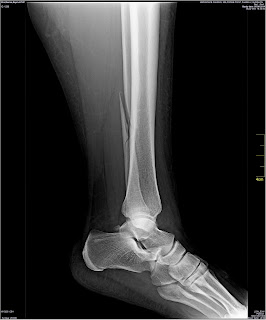

Xrays dated 9 June 2014 taken after the ankle was twisted which show a dislocated ankle.

Xrays taken on 30 July 2014 from an external lab which were shown to Dr Anuj Malhotra at Fortis Hospital on 30 July 2014.